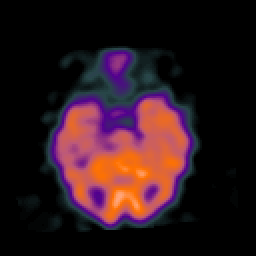

Normal aging, overlay -- Slice #19